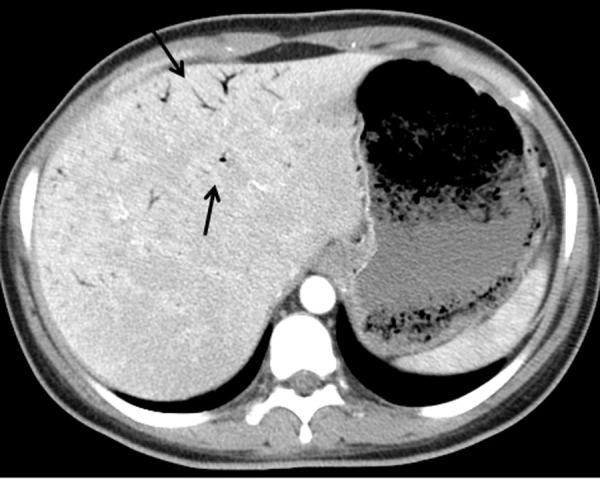

Emphysematous gastritis with portal venous air is a rare condition usually caused by gas forming organisms. This may be secondary to local spread of an infection through the mucosa or rarely hematogenous dissemination from a distant focus. We present a young diabetic woman with uncontrolled diabetes mellitus who was admitted with sepsis and severe abdominal symptoms. Investigation revealed emphysematous pyelonephritis due to E. coli infection associated with emphysematous gastritis and air in the portal tract. She improved with broad spectrum antibiotics, fluid resuscitation and electrolyte and diabetic management. To our knowledge this is the first report showing the association between emphysematous pyelonephritis and gastritis with air in the portal system.